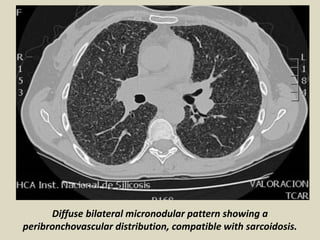

Diffuse bilateral micronodular pattern showing a

peribronchovascular distribution, compatible with sarcoidosis.